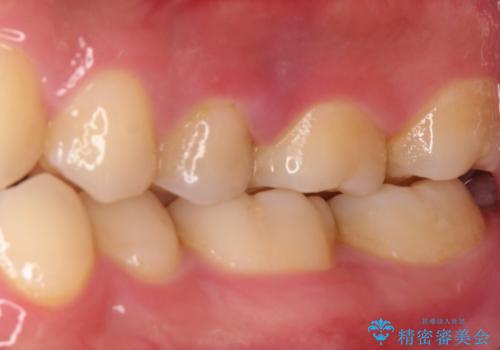

根管治療を行なったのち、オールセラミッククラウンにて修復治療を行なっております。

根管治療を行なった歯は速やかに歯冠修復が必要です。